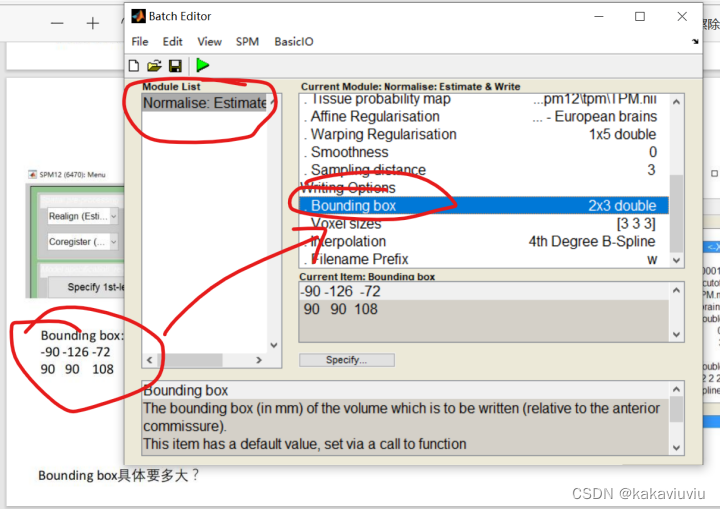

设置bounding box边界框:固定值,代表生成文件图像整体的范围是多少

修改boundingbox和体素3 3 3